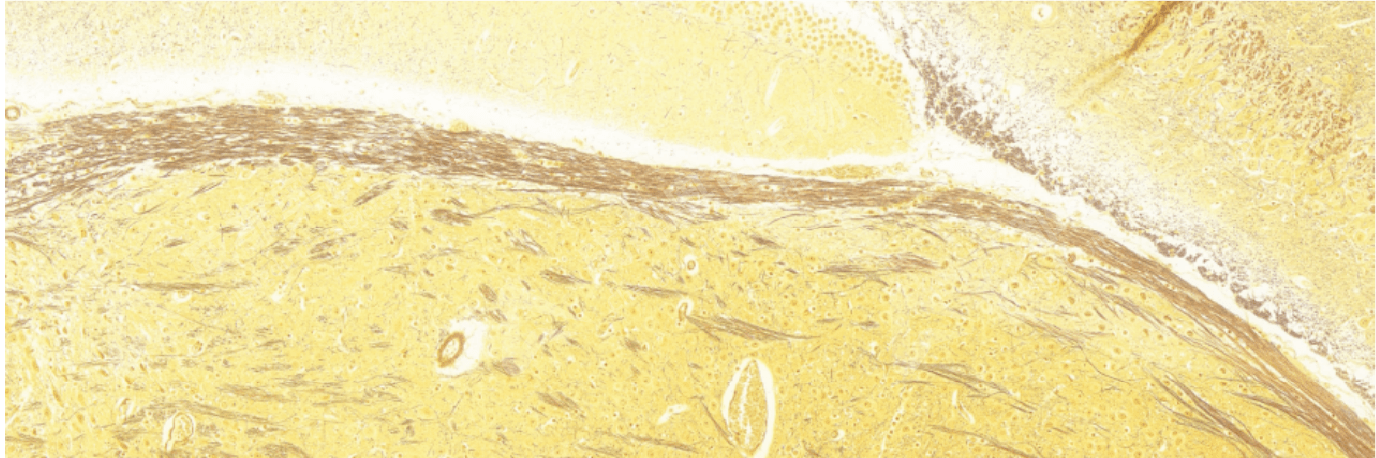

3、甘氨酸银染色:观察神经纤维

4、LFB 染色:观察髓鞘